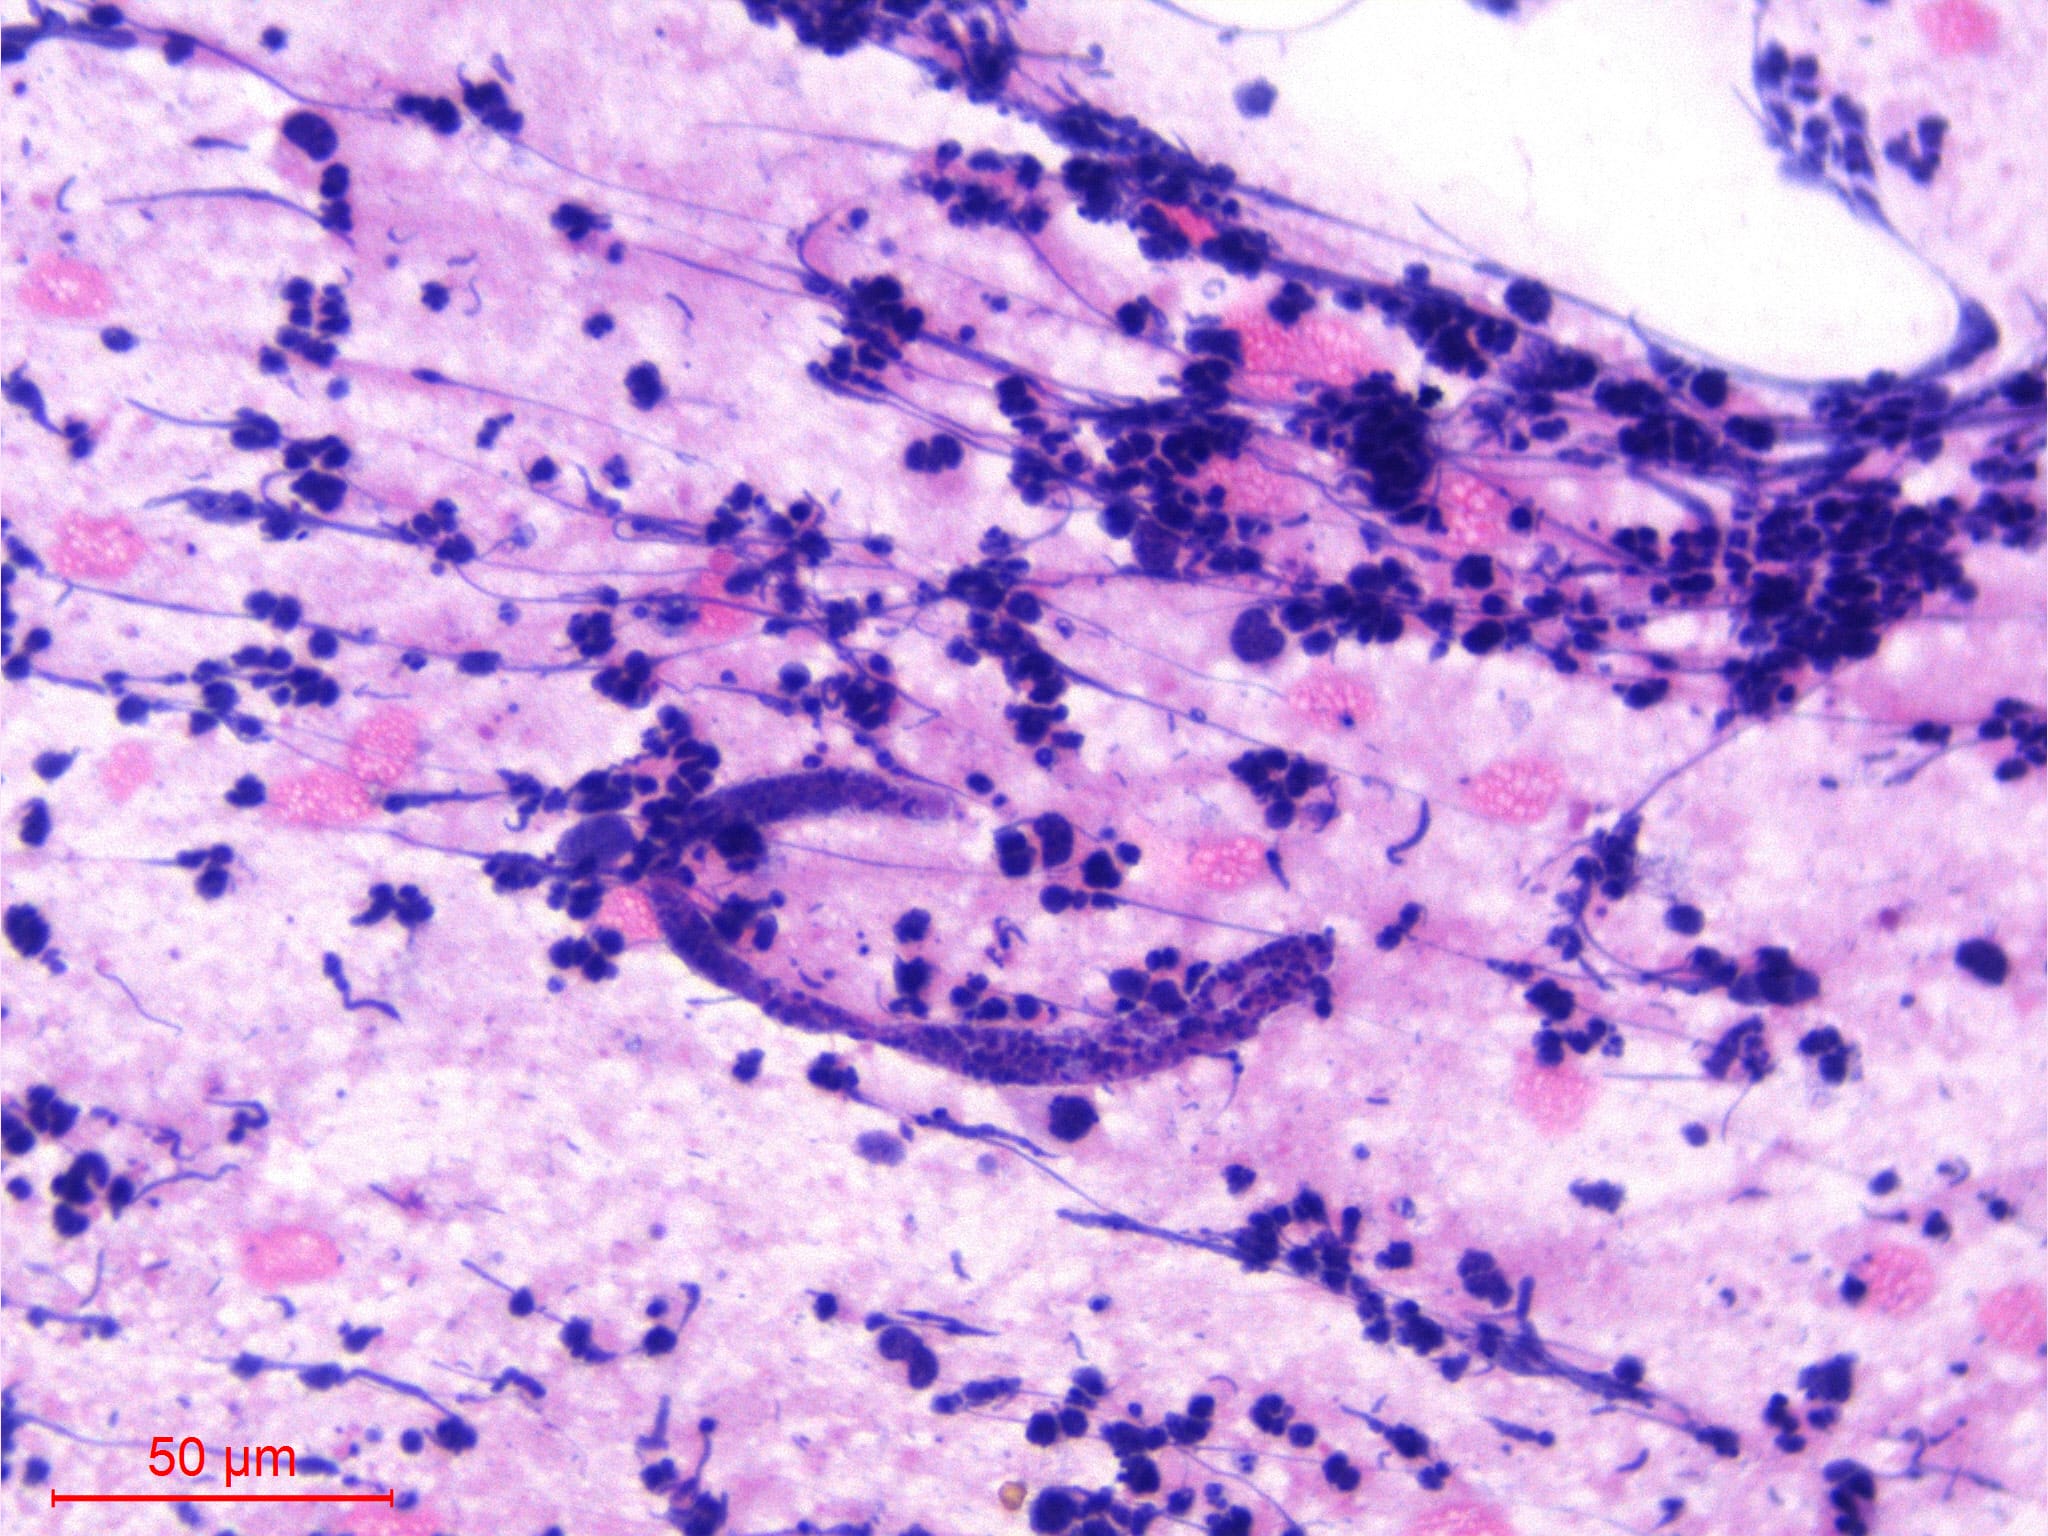

Microscopic (histologic) images

Contributed by Sajna V.M. Kutty, M.D.

Essential features

- Diagnosis is typically made by identifying microfilariae in peripheral blood smears

- Rarely, microfilariae are coincidentally detected in FNAC in association with various inflammatory and neoplastic lesions

- Wuchereria bancrofti can be identified by its sheath and multiple, coarse, discrete nuclei extending from head to tail except in the small terminal portion of the caudal end

- Diagnosis is typically made by identifying microfilariae in peripheral blood smears

- Rarely, microfilariae are coincidentally detected in FNAC in association with various inflammatory and neoplastic lesions (J Cytol 2010;27:78, J Cytol 2017;34:43)

- Finding microfilaria in cytosmears is rare

Microscopic (histologic) description

- Wuchereria bancrofti can be identified by its sheath and multiple, coarse, discrete nuclei extending from head to tail except in the small terminal portion of the caudal end

Microscopic (histologic) images

Contributed by Sajna V.M. Kutty, M.D.